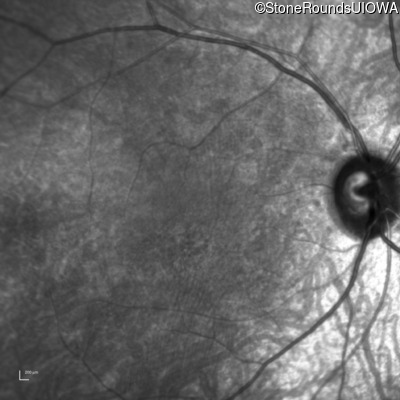

Infrared Fundus Photograph - Left - 20/100 -2 sc

Exemplar